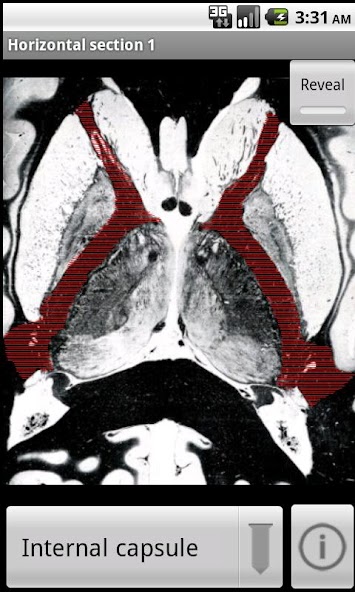

Neuroanatomy with Interactive Slices and MRI Scans of Human Brain & Spinal Cord

Learn your neuroanatomy using interactive mapped images. Each slice has neuroanatomical regions mapped out so that you can familiarise yourself with nuclei and tracts of the brain and spinal cord. I hope that NeuroSlice will be useful to training neurologists, neurosurgeons, medical students, and neuroscience students.

Neuroscan comprises 40 images taken from MRI scans and stained brain sections, which have been digitally labeled with the anatomical regions. They are all downloaded in the 6MB so you can browse offline.

1) touch a region to highlight it, and its name will be displayed

2) select the name of a region, and the region will be highlighted

3) search the database of regions to show which slices a given locus is visible.